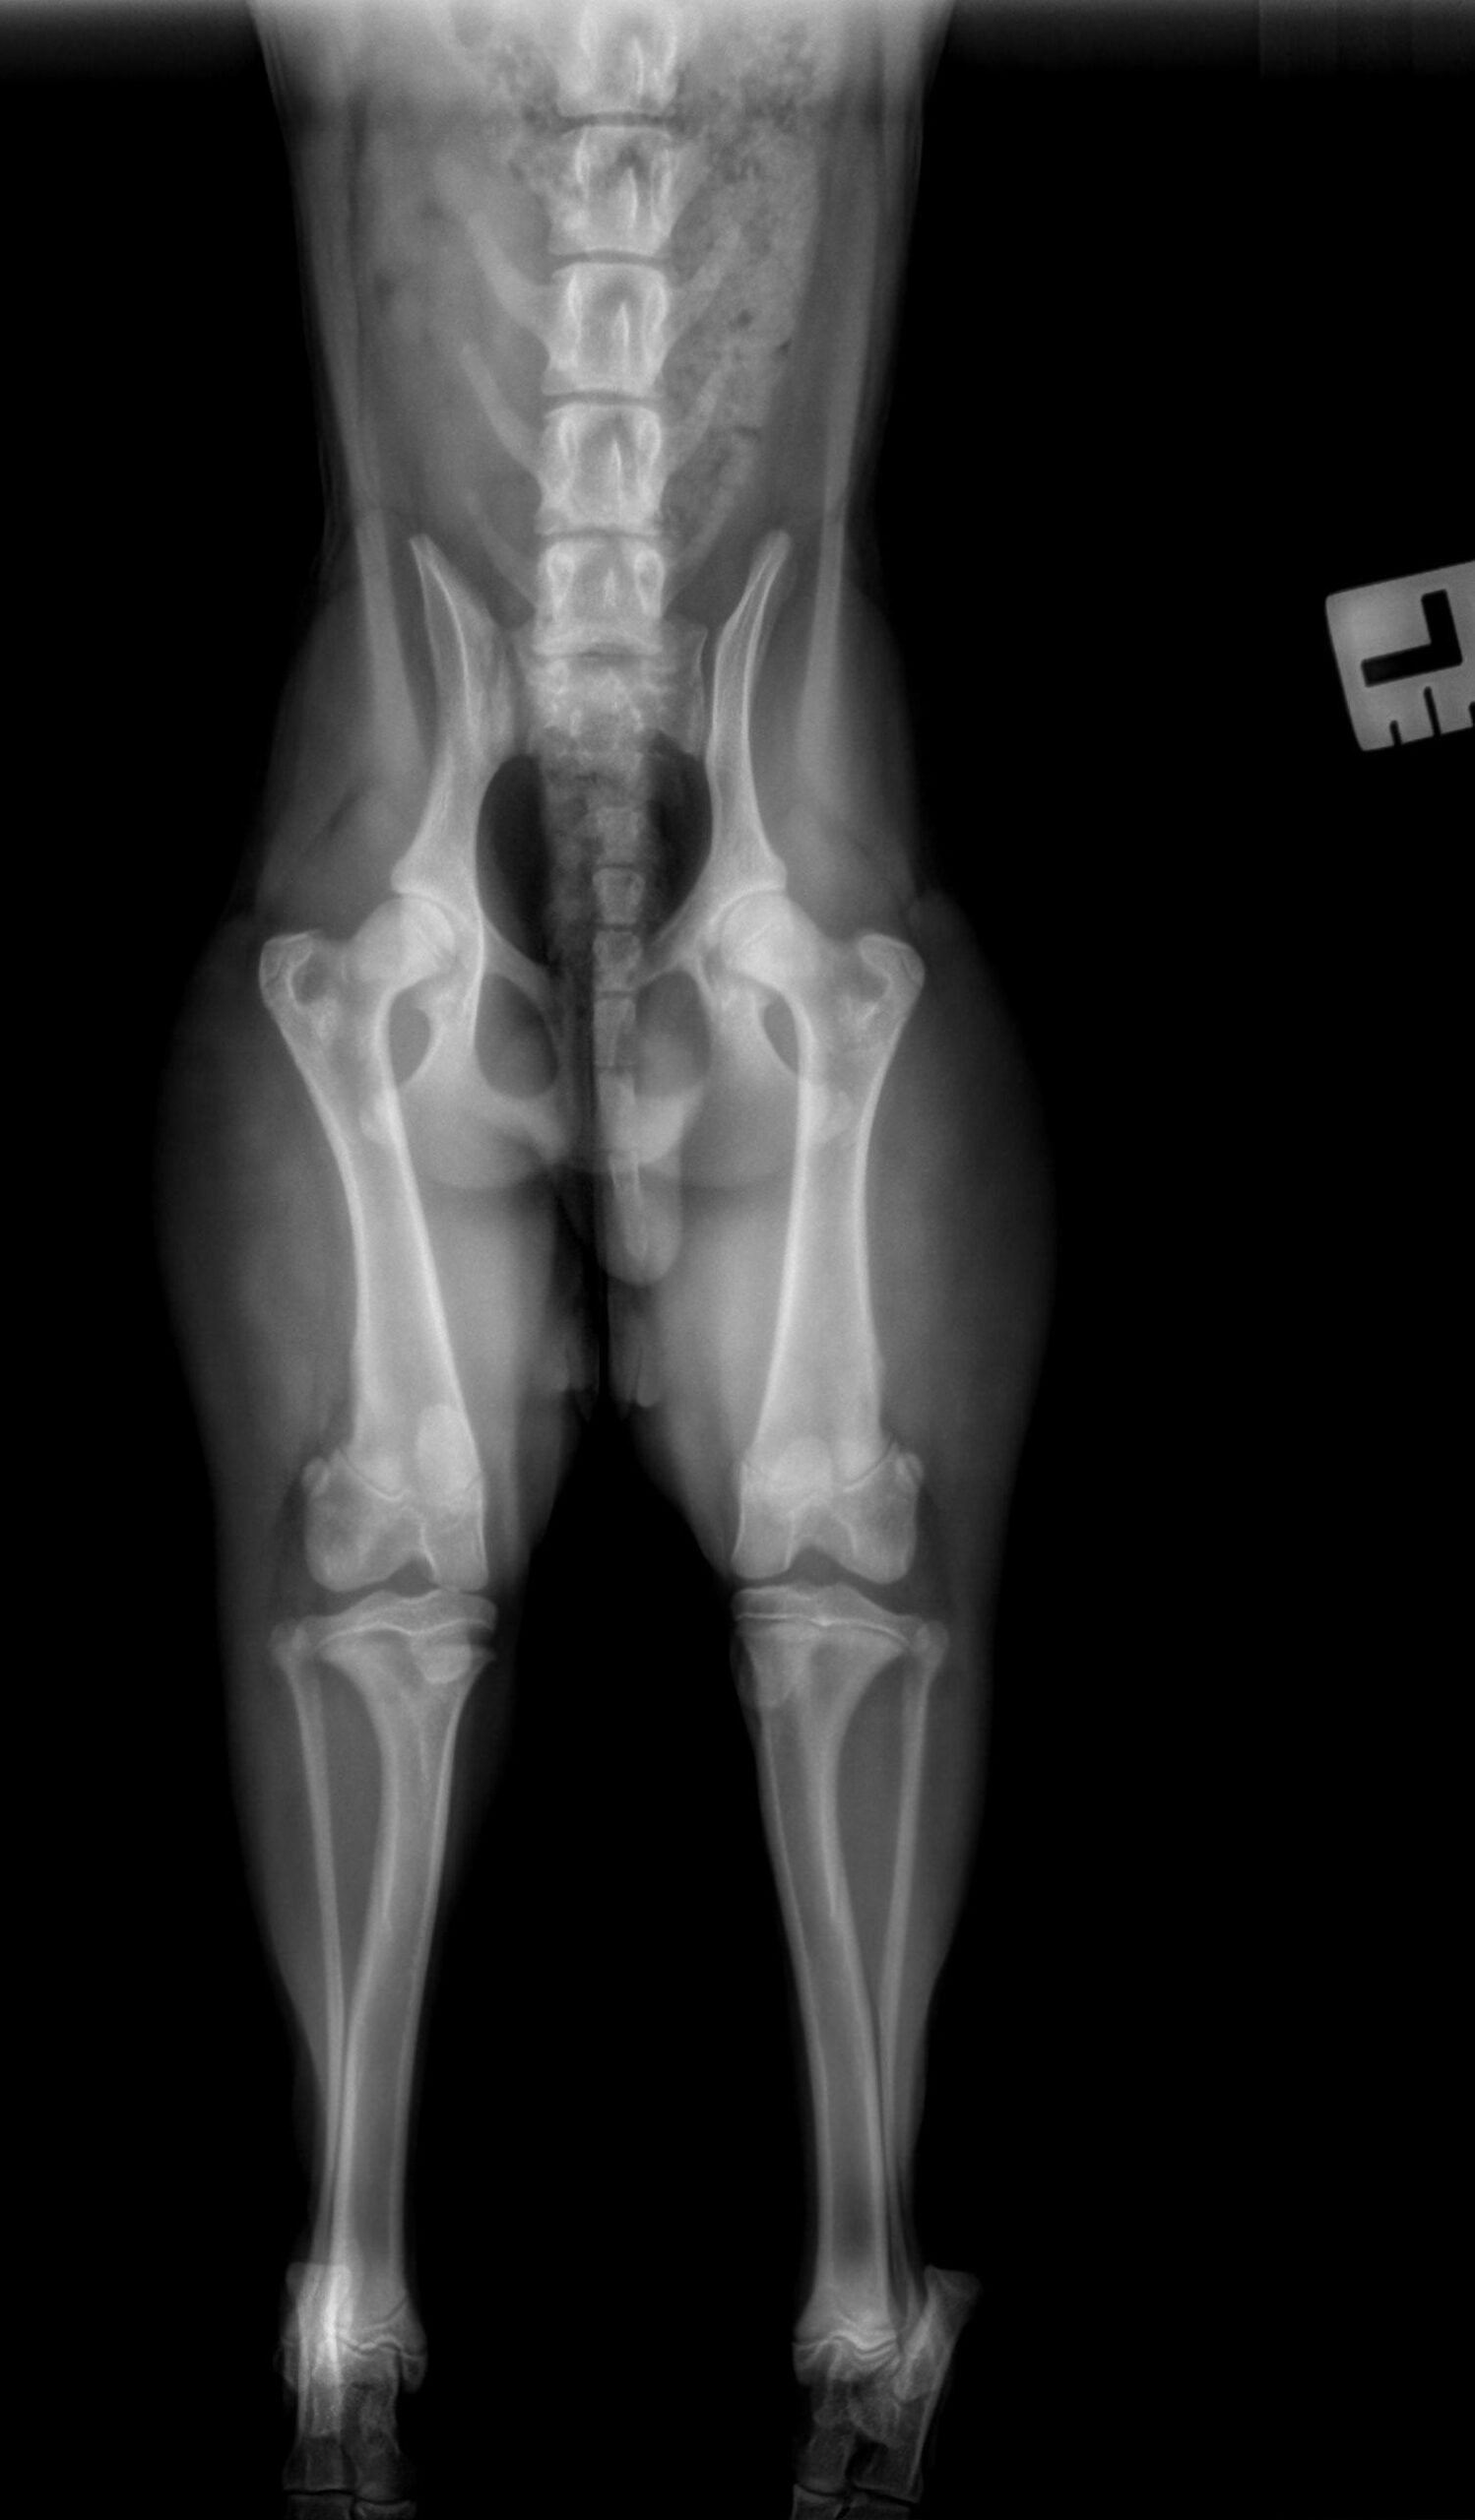

Hieronder vind je de 3 röntgenfoto’s van de achterpoten en bekken. Gebruik de pijltjes om erdoor te schuiven, of klik op de foto om te vergroten.

Er is een avulsiefractuur van de tuberositas tibiae aan de rechterpoot. De tuberositas tibiae is proximaal verplaatst en er zijn minstens enkele kleine botfragmenten zichtbaar ter hoogte van de fractuurplaats. Gelijktijdig is er een Salter-Harris type II fractuur van het caudo-proximale deel van de tibia, het best zichtbaar op de laterale opname. Het overige deel van de achterpoten is radiografisch binnen de normale grenzen.

Avulsiefractuur van de rechter tuberositas tibiae met kleine botfragmenten. Chirurgisch consult wordt aanbevolen.